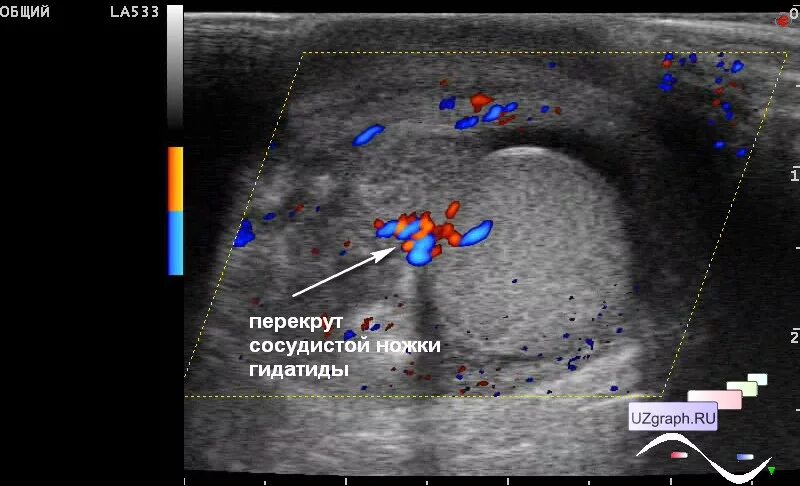

Некроз гидатиды морганьи